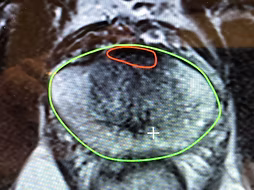

ניתוח רובוטי לכריתת ערמונית מצריך תכנון מדוקדק בטרם היציאה לדרך. הסיבה לכך היא שאנו צריכים להסיר את כל הגידול ובמקביל לשמר ככל האפשר את השליטה על השתן ואת התפקוד המיני. לשם התכנון אשתמש בתוצאות "ביופסיית המיפוי הטרנס פרינאלית מצומדת ה MRI" אותה ביצענו. מהבדיקה אקבל מפת דרכים שתאפשר לי בבטחון לתכנן באילו אזורים ליטול שולי בטחון רחבים ובאילו אזורים להתקרב לערמונית ולשמר מבנים חשובים כגון הסוגר והעצבים. מפה זו תאפשר לי גם לתכנן את ווריאציית הניתוח (למשל שימור צוואר כיס השתן). במידה וביצעת ביופסיה רגילה במקום אחר אבקש כי תשלים בדיקת MRI.